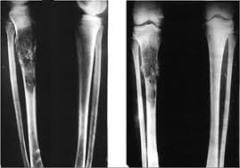

Остеосаркома. Наиболее часто встречающийся вид рака костей, который затрагивает кости верхних и нижних конечностей, и кости таза. Опухоль начинает развиваться в клетках костной ткани. Обычно встречается у детей и молодых людей до 30 лет. Иногда диагностируется у людей 60-70 лет. Данная опухоль чаще встречается у мужчин, чем у женщин.

В диагностике данного заболевания определяющей называют триаду таких признаков рака костей — болевой синдром в области поражения, существование там же ткани новообразования и нарушение основных функций конечности.

При дальнейшем развитии заболевания появляются следующие симптомы — деформация участка тела в области опухоли или контуров пораженной конечности, часто развивается отек мягких тканей. При пальпации можно обнаружить ткань новообразования, которая обычно неподвижна относительно близлежащих мягких тканей. Нередко опухоль очень болезненна, кожа над ней горячая, что объясняется развитием воспалительного процесса. Объективные признаки рака костей появляются через 2-3 месяца после появления боли. Сначала рост опухоли достаточно быстрый, но затем он может замедлиться или вообще прекратиться. Определяемая при пальпации опухоль указывает на распространение опухолевого процесса в близлежащие мягкие ткани. Кожа, которая покрывает опухоль большого размера, утончается, становится бледной с заметным рисунком расширенных вен. Такие опухоли редко прорастают в кожу.